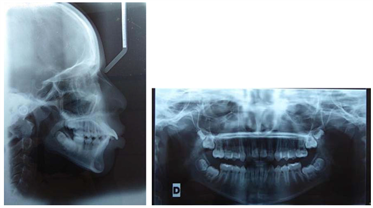

4.4. Treatment Results

Records post treatment show improvement in profile convexity (Figure 16), Class I skeletal relationship, Class I canines and molars, reduction in ANB angle (Table 3), improvement in the anteroposterior position of the mandible, and correct alignment of the teeth. We were therefore able to achieve the majority of the patient’s treatment goals. (Figure 17 and Figure 18)

Figure 17. Pre-treatment lateral cephalogram and panoramique radiographs.